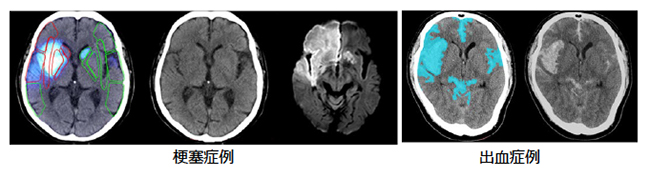

ディープラーニング等を用いて設計・開発した技術により,頭部単純CT画像から周囲と比べ低コントラスト及び高輝度の領域を自動で強調表示する。これらは,脳卒中の画像診断において,脳内の出血領域や初期虚血変化等を評価するために用いられる。今後他の疾患へアプリケーションの幅を広げることで,様々な診断支援に活用できる。また,同社PACSと組み合わせることで,医師がワークリスト上で処理状況を確認できる機能や,処理結果をインタラクティブに操作できる機能といった一貫した操作性により,画像診断ワークフローの改善に貢献する。